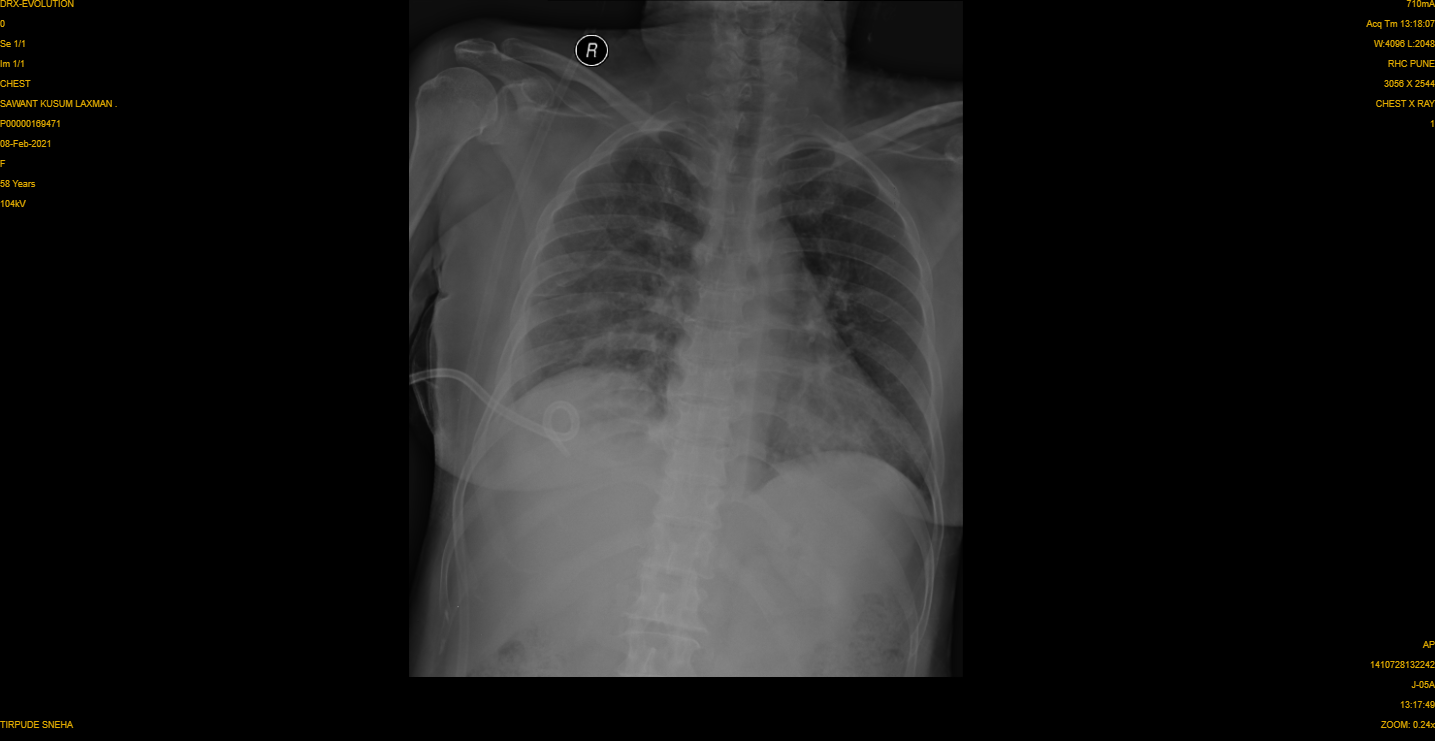

| Chest X Ray showing right white lung |

A 60 year old lady had increased breathlessness and cough since few days.and had decreased breathing sounds on hearing with stethoscope. Her Chest X Ray showed almost complete white lung on right side. We suspected a right sided fluid collection in pleura (the lung covering) versus a Lung cancer mass/Lung Abscess (fluid filled cavity), or even a hydatid cyst